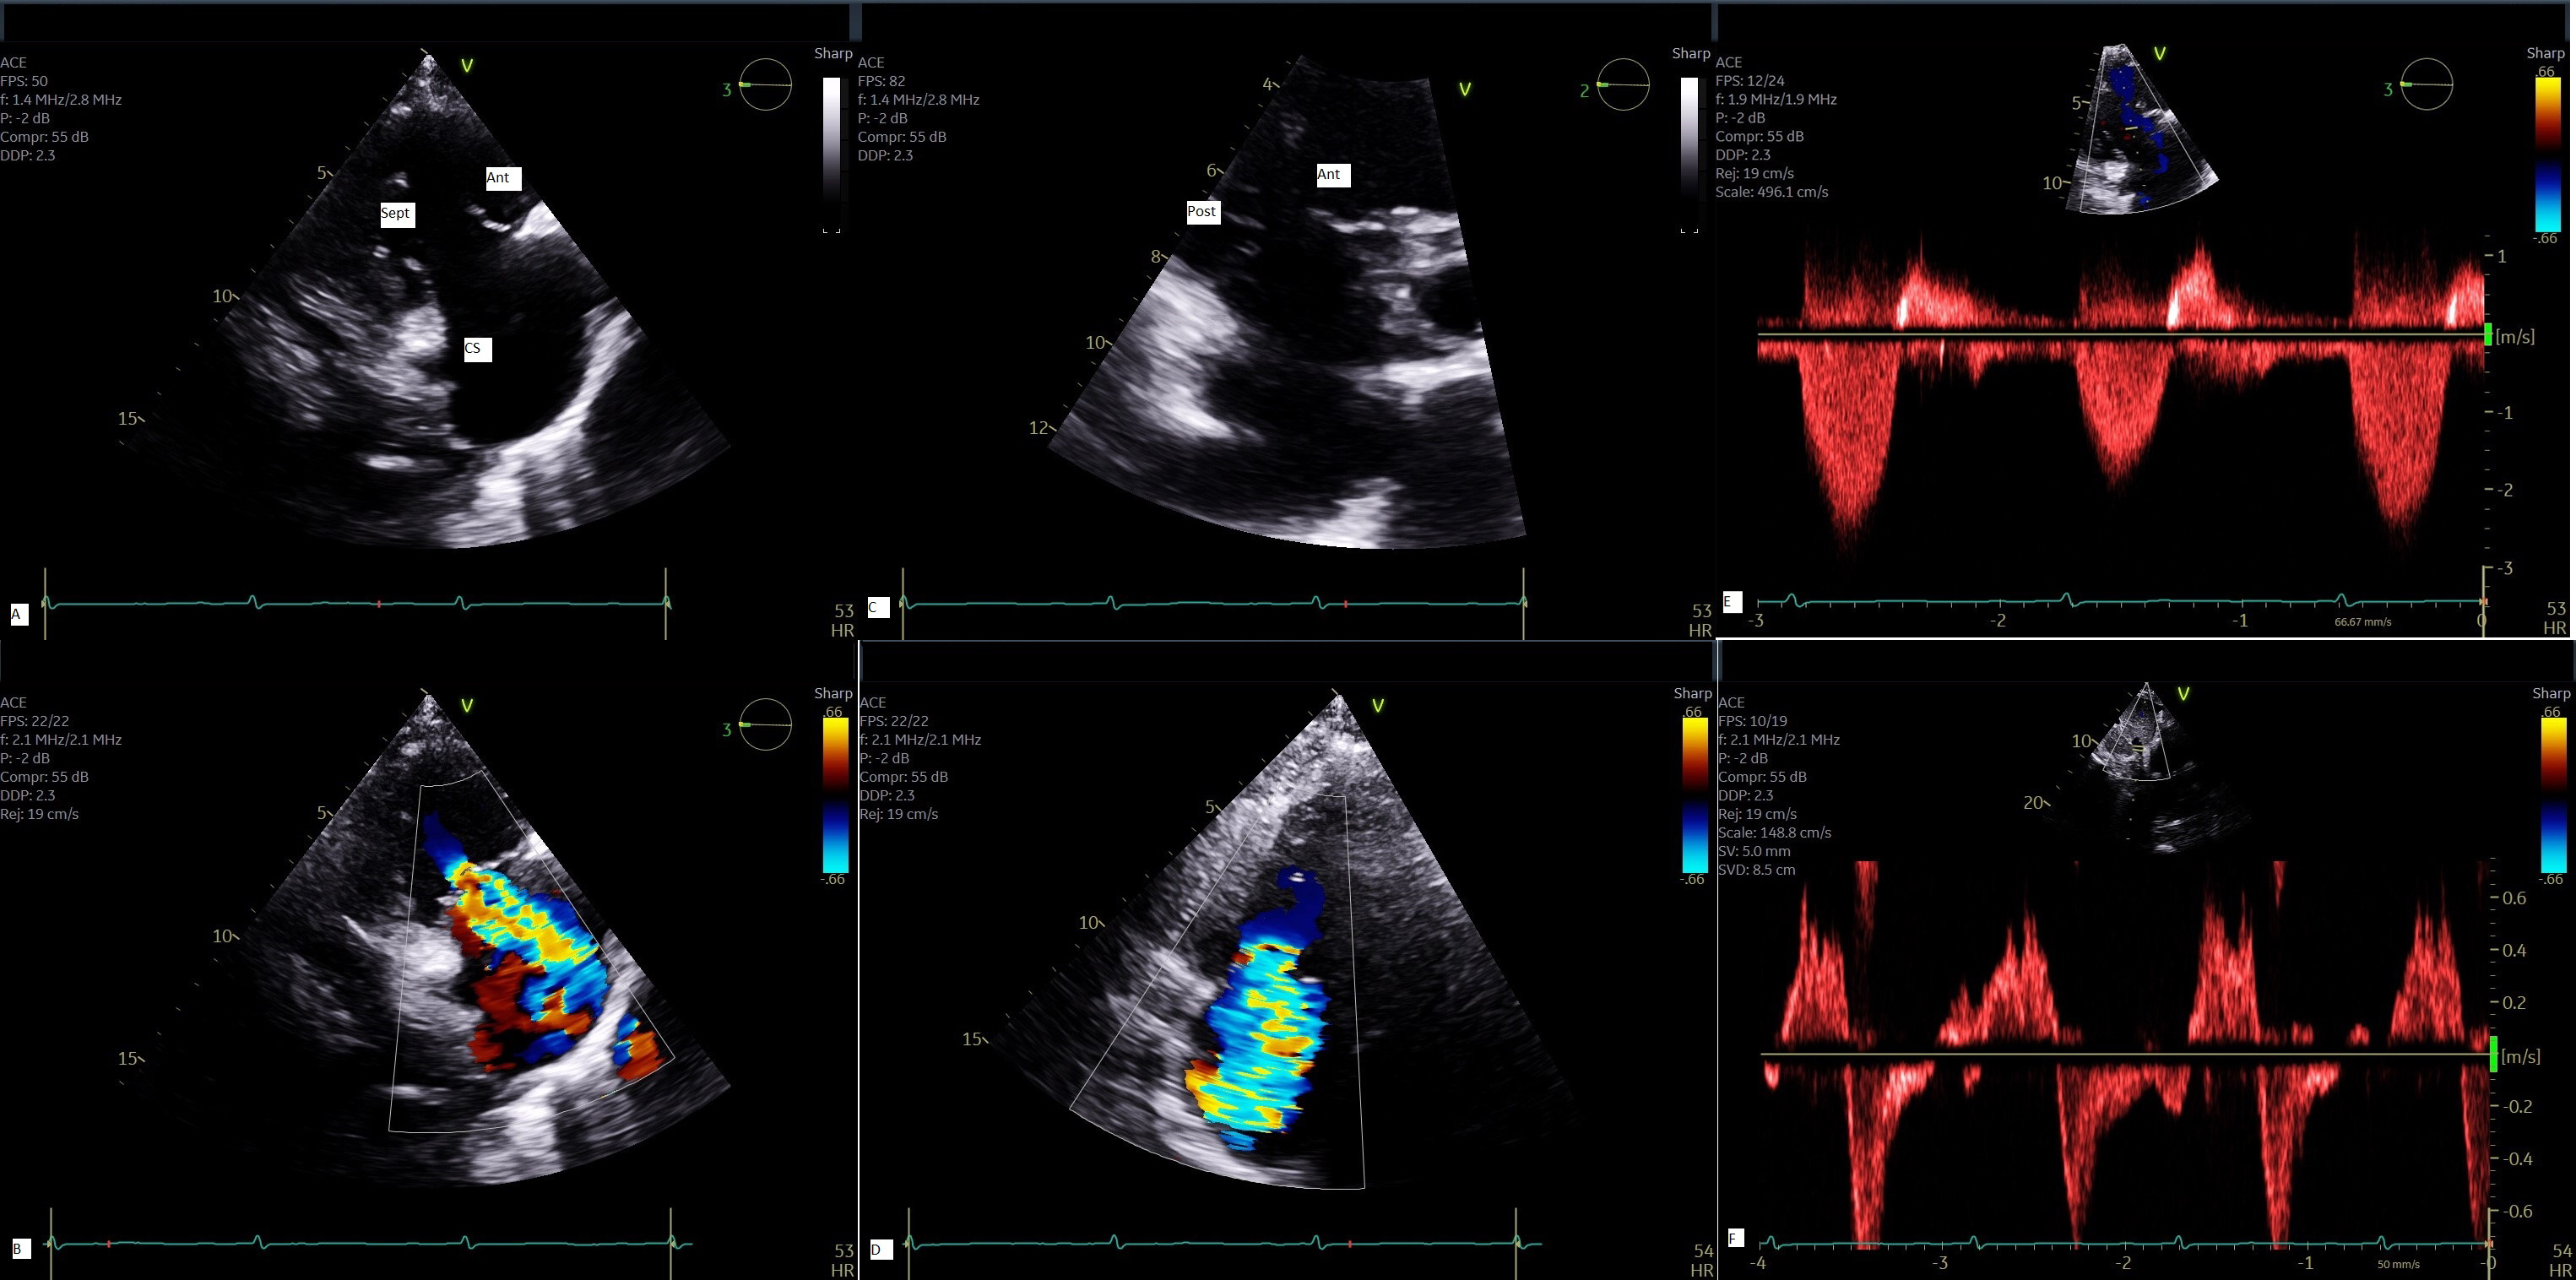

Fig. 3.

Multi-parametric assessment of TR by TTE. 2-D view of tricuspid valve from parasternal RV long axis (A) with color flow Doppler of TR jet (B); 2-D view of tricuspid valve from parasternal short axis (C) with color flow Doppler (D); Continuous wave Doppler demonstrates a triangular envelope (E) and systolic flow reversal in hepatic vein by pulsed Doppler (F) all characteristic of severe TR. Ant, anterior leaflet; Sep, septal leaflet; Post, posterior leaflet; CS, coronary sinus; 2D, 2-dimensional; TTE, transthoracic echocardiography.